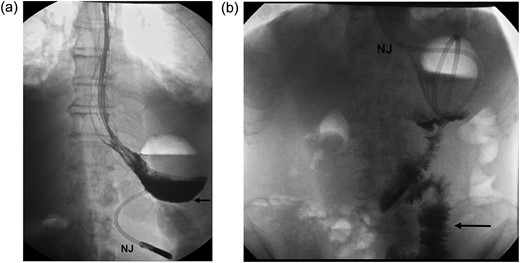

A 65-year-old female patient had undergone repair of a large hiatus hernia by laparoscopy with posterior cardiopexy and 360° fundoplication. Routine contrast swallow on Day 1 showed good passage of contrast through the fundoplication (Fig. 1a). On Day 2 post-operatively, saliva regurgitation occurred and repeat contrast study revealed a hold up at the level of the wrap (Fig. 1b). Intravenous dexamethasone (Merck Sharp & Dohme Laboratories-Chibret, France) administration at a dose of 8 mg daily was instituted for 72 h. Forty-eight hours later, oral fluid was tolerated allowing discharge and diet was upgraded to full fluids a week later. Recovery was progressive and uneventful with return to normal diet.

(a) Contrast swallow on Day 1 following posterior cardiopexy and 360° fundoplication demonstrating adequate passage of contrast through the wrap (W=right and left folds of the wrap). (b) A repeat contrast swallow in the same patient 24 h later revealing a hold up at the level of the wrap caused by oedema. The oesophagus above the wrap is dilated. A thin trickle of contrast (black arrow) is seen to come through the fundoplication.